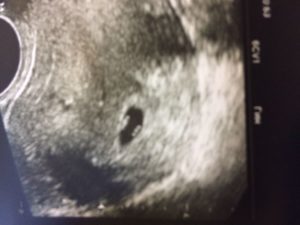

Ультразвук фиксирует количество эмбрионов в конце первого месяца беременности. 5 неделя — время прикрепления эмбриона к стенке матки. Раннее УЗИ проводится с целью определения типа беременности: маточная или внематочная.